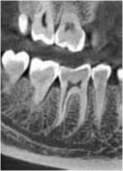

当診療所では、歯科用3Dパノラマ撮影装置(エクセラスマート F+)を導入しております。

これまで以上に、より正確に患部の状態を把握できるようになり、患者様に精度の高い、安全で確実な歯科診療を提供することができるようになりました。

①高画質

従来に比べ、より高画質で高精度の画像撮影が可能に。

歯根の形態から上顎洞・顎関節等に至るまで、総合的により細部の把握が可能になり、1枚の写真で的確な診断が容易にできるようになりました。

小型:最小80μmの

ボクセルサイズを実現

歯根の形態や根尖方向などの

細部の撮影~把握が可能です。